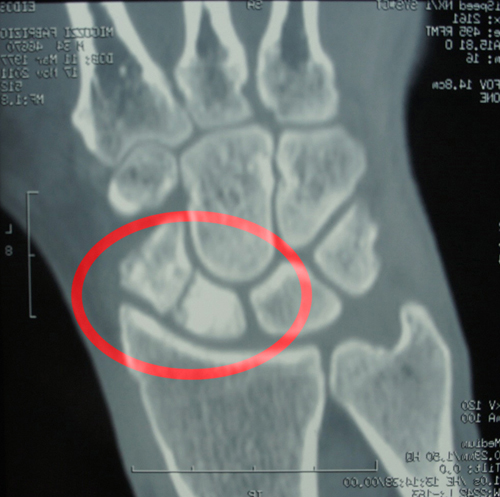

Sintomi della frattura dello scafoide del piede. Se la frattura altera la normale vascolarizzazione ossea, è altamente probabile che lo scafoide vada incontro a osteonecrosi. Sintomi ossa del piede dipartimenti.

La frattura dello scafoide è provocata da traumi diretti sulla mano, ad esempio una caduta in avanti con il polso in iperestensione, cioè nella posizione in cui si riceve un.

Dopo una frattura dello scafoide del piede, quando si potrà ricominciare ad appoggiare il piede? Quindi, l'osteonecrosi è una complicazione comune, a volte invalidante. I sintomi possono includere dolore e gonfiore intorno al polso. L'infortunio tende a peggiorare nel tempo. Ott 25, 2012 | disturbi della mano, mano: La tabacchiera anatomica è generalmente tenera e può verificarsi gonfiore. Le fratture dello scafoide di solito causano dolore e gonfiore alla base del pollice. Questo osso posizionato nel polso è piccolo e difficile da inquadrare. Ecco perchè devi sempre affidarti ad un medico: I sintomi di questo trauma sono un edema posterioredipartimento di piede e la rapida comparsa di ematoma. In questo video scoprirai cos'è il quinto metatarso, come si presenta la frattura di questo osso e i tempi di recupero. Caro signore, la frattura dello scafoide è sempre u problema purtoppo, visto che la vascolarizzazione è precaria e quindi la consolidazione non è sempre garantita salve, in seguito ad accertamenti, la mia frattura con distacco parcellare dello scafoide in realta è risultata essere un distacco parcellare dello. Si avverte dolore nella cosiddetta regione della tabacchiera anatomica (quell'avvallamento che compare sul dorso della mano, quando è aperta, tra polso e pollice) e solo di rado c'è anche gonfiore. Quello che chiedo è, darò che non mi è stata fatta alcuna ecografia risonanza magnetica, dai sintomi descritti, potrebbe esserci una frattura dello scafoide non rilevata dalle rx? Le complicanze possono includere mancata unione della frattura. La frattura del piede è un evento molto comune che consiste nella rottura di una delle ossa del piede: Numerosi studi sono stati condotti sulle fratture dello scafoide e sulle relative tecniche di immobilizzazione,e si e' giunti ad un accordo che prevede la corretta.